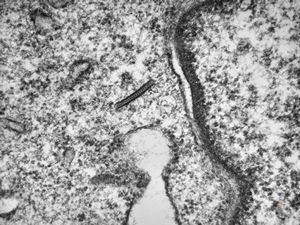

M, 1y. | histiocytosis X (eosinophilic granuloma) - Birbeck body

M, 1y. | histiocytosis X (eosinophilic granuloma) - Birbeck body

M, 7m. | hhistiocytosis X (eosinophilic granuloma) - Birbeck bodies

M,7m. | histiocytosis X (eosinophilic granuloma) … formation of Birbeck body

M, 7m. | histiocytosis X (eosinophilic granuloma) - Birbeck body

M, 1y. | histiocytosis X (eosinophilic granuloma) - Birbeck bodies